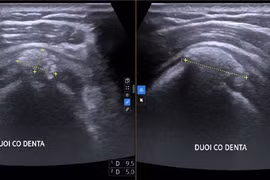

Đau vai cả tháng, người phụ nữ phát hiện viêm gân vôi hóa

Viêm gân vôi hóa thường gặp ở nữ giới trung niên, gây các cơn đau dữ dội, ảnh hưởng đến sinh hoạt và chất lượng cuộc sống.